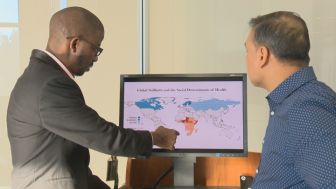

Gender inequality a major contributor to global stillbirths, Saskatchewan study findsThe rate of stillbirths around the world varies greatly. Now, new research from the University of Saskatchewan suggests a major factor in the disparity is gender inequality.HealthFeb 5, 2020